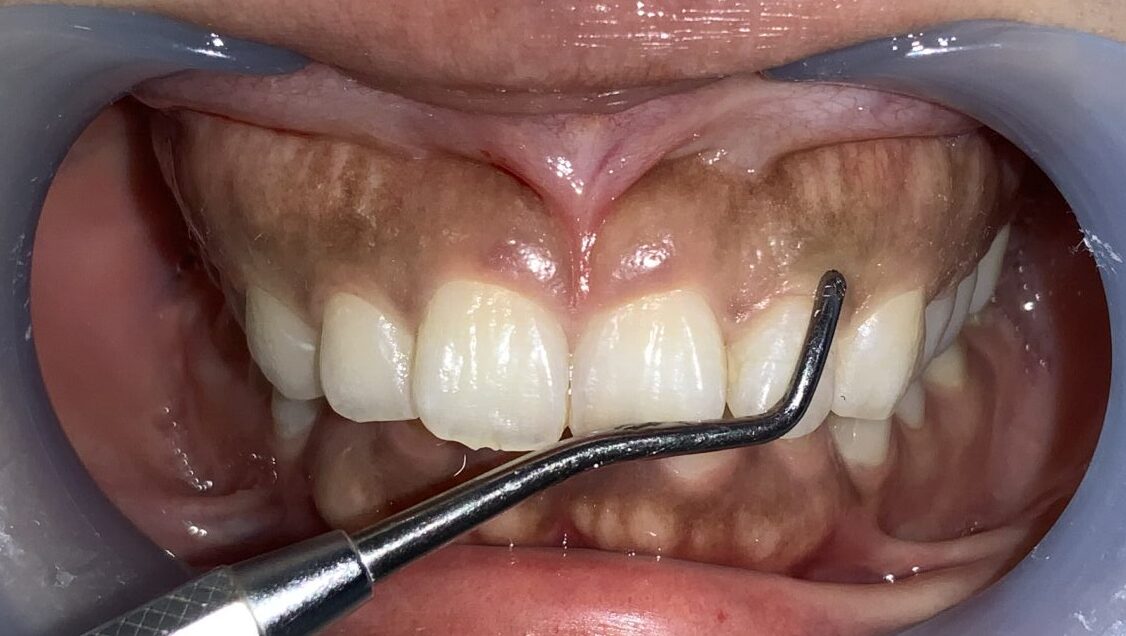

反対側の前歯です。

こちらもたくさんかぶっています。歯槽骨のとがった部分もあり、ざらざらした面もありますから、歯槽骨整形も同時に行う必要がありそうです。

前歯に戻って反対側です。

こちらも歯槽骨のざらざら感や、とがった部分がありそうです。